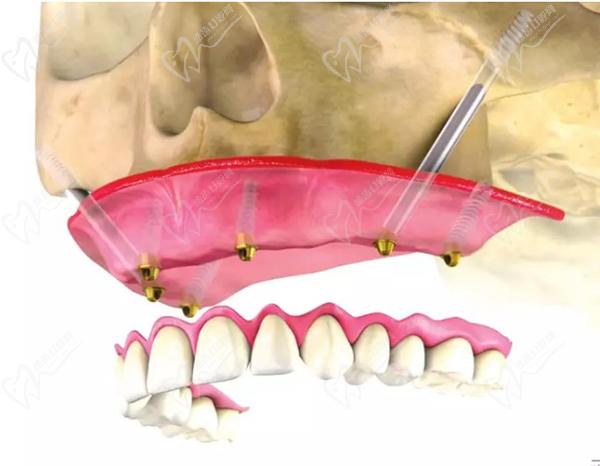

第四步:戴牙冠

医生会进行口腔扫描,以获得足够的精 确度来制作牙冠。牙冠将在实验室制作,以匹配患者的牙齿和嘴型。设有数字化全息一体牙冠制作中心的正规口腔医院,等在短短2小时内就完成牙冠的定制设计和制作哟。我们将在下面着重讨论种植体材料和价格的问题。

第五步:牙冠装配

装配过程通常被视为一个紧急过程,可以在接下来的几小时或几天内完成。医生将确定所有材料是否适合,并调整和调整新牙齿到正确的位置。